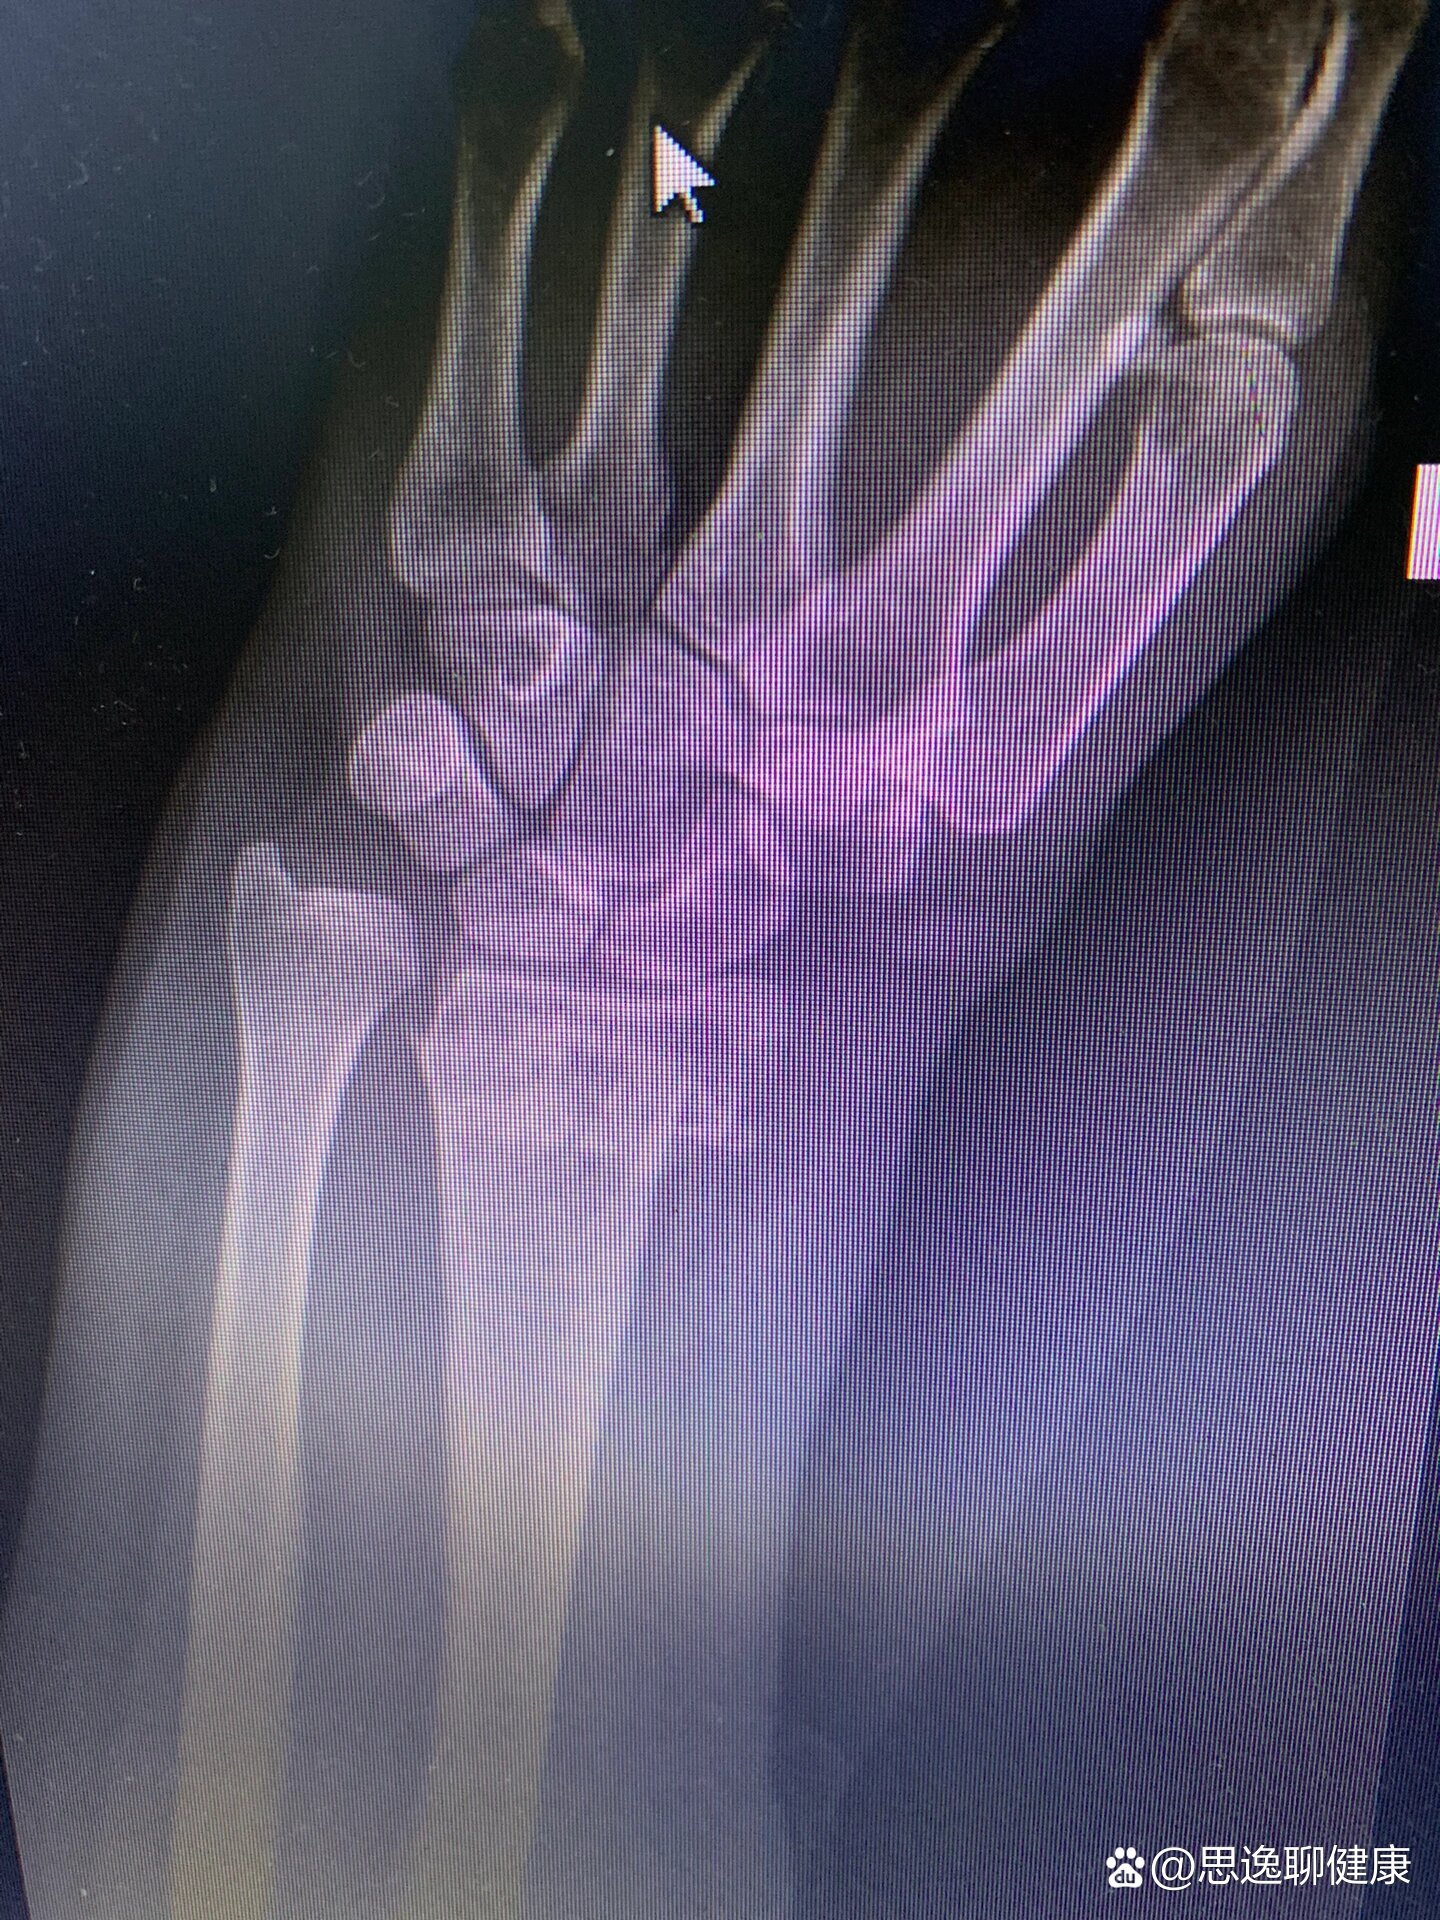

尺桡骨远端骨折完全移位折顶复位

图片尺寸1205x541